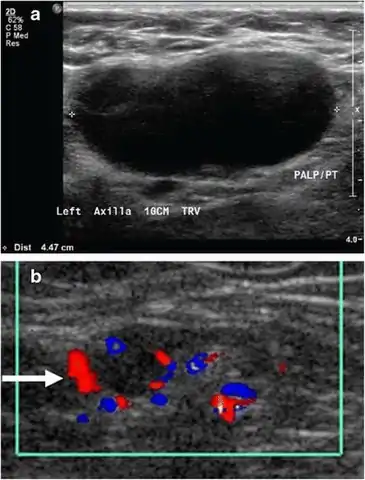

- Absence of the fatty hilum

- Increased focal cortical thickness greater than 3 cm

- Doppler ultrasonography that shows hyperaemic blood flow in the hilum and central cortex and/or abnormal (non-hilar cortical) blood flow.[25]

On ultrasound, B-mode imaging depicts lymph node morphology, whilst power Doppler can assess the vascular pattern.[27] B-mode imaging features that can distinguish metastasis and lymphoma include size, shape, calcification, loss of hilar architecture, as well as intranodal necrosis.[27] Soft tissue edema and nodal matting on B-mode imaging suggests tuberculous cervical lymphadenitis or previous radiation therapy.[27] Serial monitoring of nodal size and vascularity are useful in assessing treatment response.[27]

Lymphadenopathy of the axillary lymph nodes can be defined as solid nodes measuring more than 15 mm without fatty hilum.[35] Axillary lymph nodes may be normal up to 30 mm if consisting largely of fat.[35]